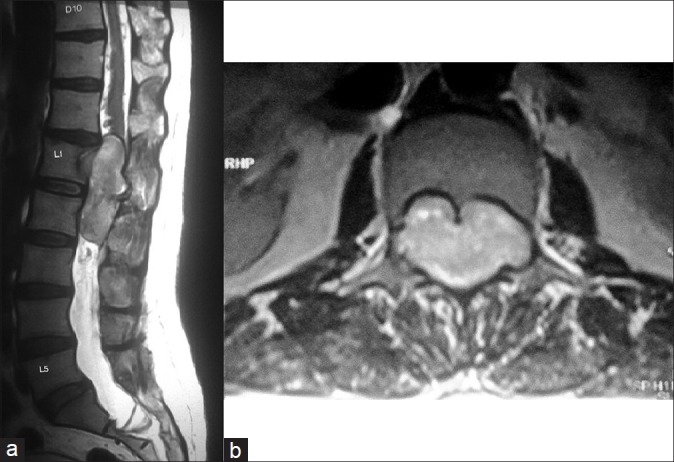

脊髓空洞综合征(Conus-cauda syndrome)是由于脊髓下端和神经根束受累所致。常见的病因是外伤、椎管狭窄、脊髓肿瘤、炎症和感染性疾病,但副神经节瘤是一种罕见病因。这些肿瘤很少具有分泌儿茶酚胺的功能。据我们所知,迄今为止只有五例功能性脊髓副神经节瘤的病例报告。我们报告了一名 50 岁的男性高血压患者,其病变呈分叶状,从 D12 下缘延伸至 L2,术前影像学检查报告为上皮瘤。该病变在术后被证实为功能性副神经节瘤,而患者因该病变引起的严重并发症而死亡,因此凸显了术前诊断和处理的重要性。总之,锥尾功能性副神经节瘤非常罕见。从内科和外科治疗的角度来看,在术前对其进行诊断至关重要。在手术过程中,应非常小心地处理这些肿瘤,以避免儿茶酚胺进入血液。这些肿瘤在围手术期需要麻醉师和内分泌专家的协助。

Conus-cauda syndrome is caused due to involvement of the lower end of the spinal cord and arising bunch of nerve roots. It is caused commonly due to traumatic injury, spinal stenosis, spinal tumors, inflammatory, and infectious conditions, but paraganglioma is a rare cause. These tumors are rarely functional and secrete catecholamine. Till now only five case reports of functional spinal paragangliomas are available to the best of our knowledge. We report a 50-year-old hypertensive male patient with a lobulated lesion extending from lower border of D12 to L2, which was reported as ependymoma on imaging studies done preoperatively. This lesion was confirmed to be a functional paraganglioma postoperatively after the patient died because of its furious complication, thus highlighting the importance of its preoperative diagnosis and management. In conclusion conus-cauda functional paragangliomas are very rare entity. Diagnosing them in preoperative condition is critical from the therapeutic point of view, both medical and surgical. During surgery these tumors should be handled very gently to avoid spillage of catecholamines into blood. These tumors require assistance of expert anesthetist and endocrinologist in the perioperative period.